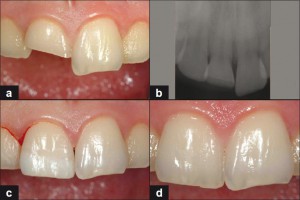

- II klasa – prelom gleđi i dentina

- III klasa – prelom gleđi i dentina sa povredom pulpe

U slučajevima I i II klase preloma zuba terapija podrazumeva nadogradnju krunice estetskim materijalima već u prvoj poseti stomatologu.

U težim slučajevima III i IV klase ishod terapije zavisi od stepena resorpcije(kod mlečnih), odnosno stepena razvitka korena(kod stalnih zuba) tj. da li je zub sa nezavršenim ili završenim razvitkom korena, od širine otvora pulpe kao i od proteklog vremena od momenta povrede do dolaska u stomatološku ordinaciju.